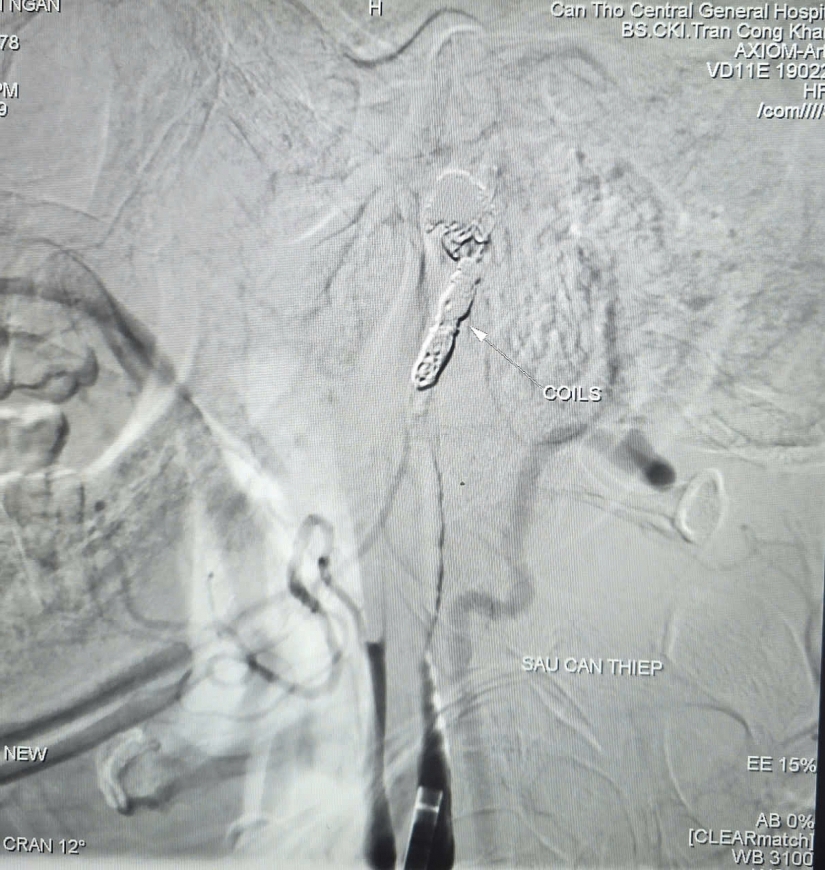

Không còn hình ảnh thoát mạch của bệnh nhân sau can thiệp

Ê-kíp tiến hành bóng chẹn dòng chảy để kiểm soát lượng máu, sau đó luồn vi ống thông siêu nhỏ tiếp cận chính xác vị trí túi phình. Các bác sĩ đã thả 9 vòng xoắn kim loại (coils) nhằm gây tắc hoàn toàn ổ giả phình và động mạch cảnh trong phải, qua đó kiểm soát triệt để nguồn chảy máu.

Kết quả chụp kiểm tra từ động mạch cảnh trong trái cho thấy hệ thống tuần hoàn bàng hệ nuôi não phải thông qua động mạch thông trước, bảo đảm tưới máu não sau can thiệp. Toàn bộ thủ thuật được hoàn tất trong 90 phút.